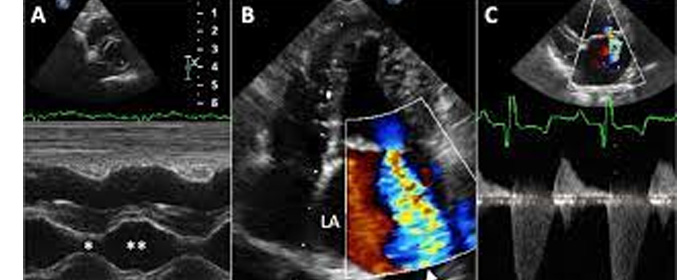

Doppler echocardiography is a procedure that uses Doppler ultrasonography to examine the heart. An echocardiogram uses high frequency sound waves to create an image of the heart while the use of Doppler technology allows determination of the speed and direction of blood flow by utilizing the Doppler effect.

An echocardiogram can, within certain limits, produce accurate assessment of the direction of blood flow and the velocity of blood and cardiac tissue at any arbitrary point using the Doppler effect. One of the limitations is that the ultrasound beam should be as parallel to the blood flow as possible. Velocity measurements allow assessment of cardiac valve areas and function, any abnormal communications between the left and right side of the heart, any leaking of blood through the valves (valvular regurgitation), calculation of the cardiac output and calculation of E/A ratio (a measure of diastolic dysfunction). Contrast-enhanced ultrasound-using gas-filled microbubble contrast media can be used to improve velocity or other flow-related medical measurements.